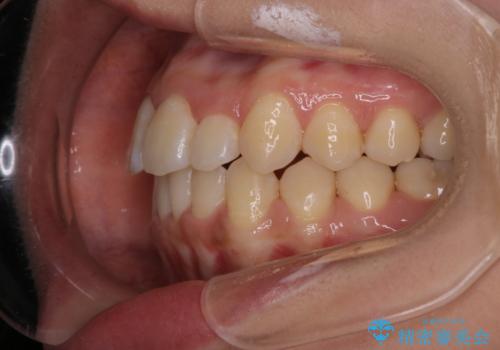

- 前歯のがたつきを治したいという主訴で来院されました。1年後に転勤の可能性があり短期間での治療を希望されました。今回は非抜歯の治療を計画し、IPRと拡大をし、前歯の叢生を改善しました。

前歯のがたつきを治しながら2番の反対咬合も改善させました。短期間で終了し満足していただけました。